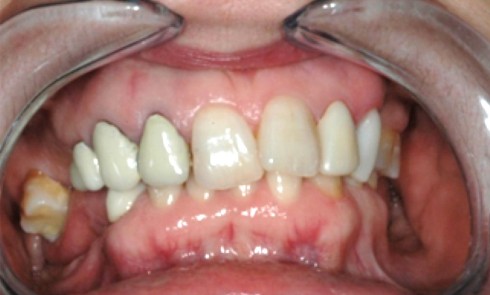

Article réservé à nos abonnés Reconstruction en antéposition

Les chirurgiens-dentistes sont parfois confrontés à des réhabilitations orales complexes. Les difficultés peuvent être dues à des délabrements ou des...